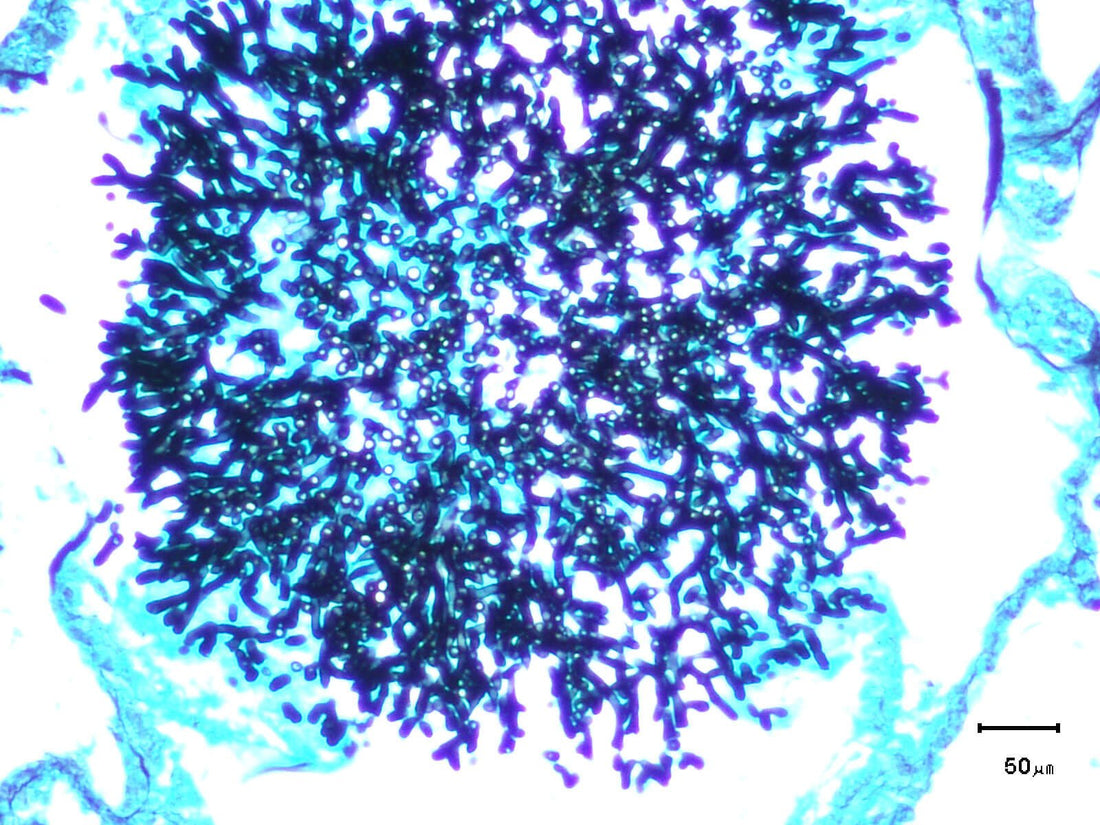

Dust presents a particular danger to birds because it can not only irritate and inflame their specialised and sensitive respiratory tract – see above – but also act as a carrier for potentially pathogenic (disease-causing) organisms including fungal spores (Figure 4. )

Figure 4. Aspergillus fungus (stained black in these pictures) can be inhaled from dusty, uncleaned, seeds and may invade the lungs, causing aspergillosis - an often untreatable disease of birds.